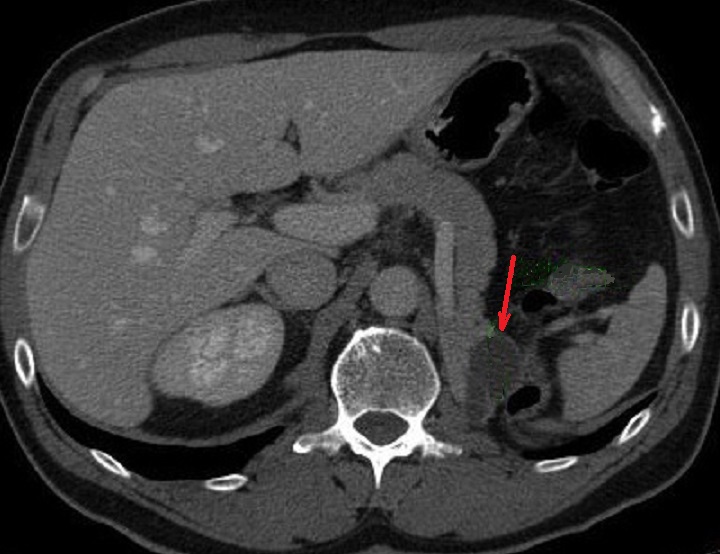

. Image radiologique TDM d'un

cystadenome sereux macrokystique situe du queue du

pancreas ( fleche rouge ) . La lesion etre mal

detecte par aspect moins hypodensite que la

parenchyme pancreatique |

Meme cas en coupe IRM

axiale ponderation sur T2 . La contenue liquidienne

du kyste devient hypersignal ( fleche jaune ) situe

au queue du pancreas |